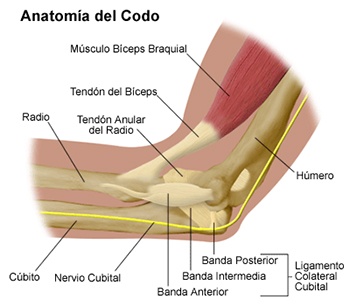

En anatomía humana, la articulación del codo es la que une el brazo con el antebrazo, conectando la parte distal del hueso húmero con los extremos proximales de los huesos cúbito y radio.

En anatomía humana, la articulación del codo es la que une el brazo con el antebrazo, conectando la parte distal del hueso húmero con los extremos proximales de los huesos cúbito y radio.

La articulación principal que constituye el codo se denomina humero radio-cubital y puede dividirse en dos partes bien diferenciadas, la articulación humero-radial y la humero-cubital.

Por otra parte el cúbito y el radio forman también una articulación entre si en las proximidades del codo, la cual se denomina articulación radio-cubital proximal.

Los extremos óseos se conectan entre si por un conjunto de ligamentos que contribuyen a su fijación y están rodeado por una estructura común que se llama cápsula articular, en cuyo interior se encuentra el líquido sinovial.